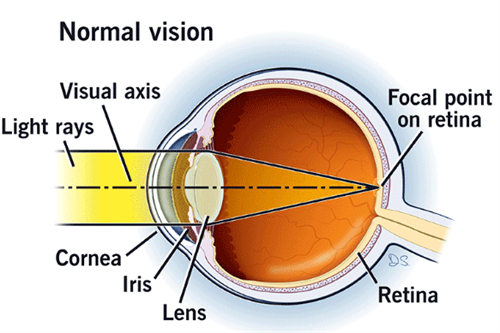

在眼科医疗领域,德国制造常被视为品质与技术的代名词。作为德国本土深耕眼科器械的品牌,德国人类光学(Human Optics)凭借其人工晶体产品,在白内障、老花眼等视力矫正领域占据重要地位。

这一设计突破了传统晶体固定光学区的限制,尤其适合高度近视、远视及合并眼底病变患者。

例如,高度近视患者因眼轴较长,常伴随视网膜变薄,动态光学区可减少对眼底的压力,降低术后并发症风险。